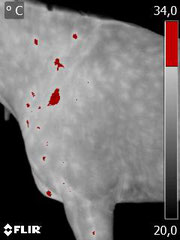

Hier sehen wir thermografisch ein gutes Bild einer leichten Schulterblockade bei einem Kundenpferd.

Blockaden in diesem Bereich haben meist vielfältige Auslöser und bedingen meist einige sichtbare Symptome, die zunächst unspezifisch erscheinen.

Durch die Thermografie können in diesen Fällen die Ursachen für solche Problematiken erkannt werden, oftmals erscheint das thermografische Bild eines Entzündlichen Bereiches der Schulter in Zusammenhang mit einer kalten Gliedmaße (Bein) vorne.